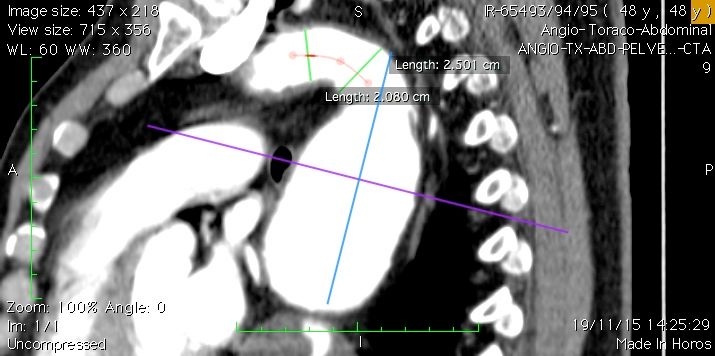

• Aneurisma da Aorta Abdominal. O que é, quem tem e como trata?

Doença Aneurismática da Aorta

Aula ministrada em 2016 aos alunos do Curso de Medicina da UFRN